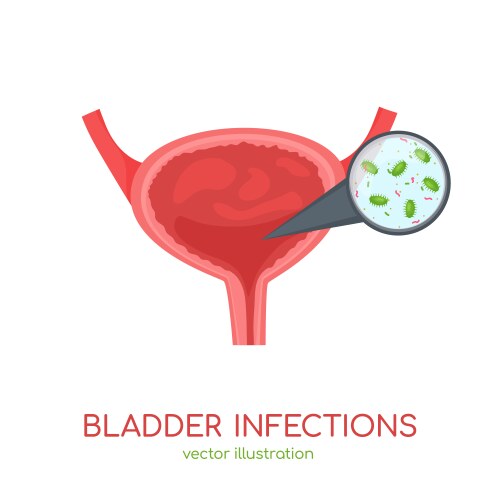

- Bladder

- Anatomy

- Organ

- Biological

- Biology

- Body

- Disease

- Health

- Medical

- Medicine

- Physiology

- Urology